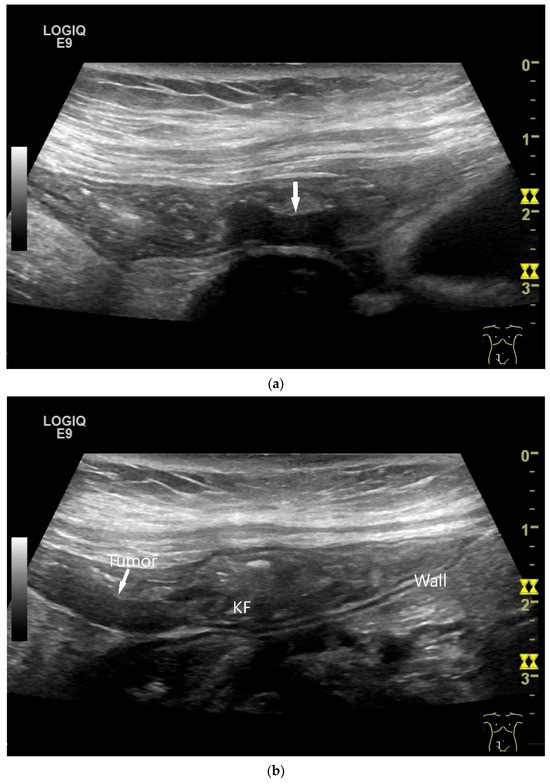

A common feature of small intestine lymphoma is a very pronounced wall thickening with marked hypoechogenicity, accompanied by enlarged lymph nodes. However, there are also focal circumscribed polypoid nodular changes or thickening of the mucosa and submucosa, which are mainly detectable endoscopically and are more difficult to delineate with cross-sectional imaging. The appearance of lymphomas in the small intestine depends on the extent of the different subtypes in the intestinal wall. The extent also depends on the stage of the disease (Figure 9 and Figure 10). Görg et al. [114] described the various manifestations of lymphoma in the gastrointestinal tract (including the small intestine) as mucosa-associated, transmural segmental, transmural circumferential, transmural nodular, and transmural bulky disease [114].

Burkitt-Lymphoma. In a patient with weight loss, increased abdominal circumference, anemia, and physical weakness, the initial sonographic examination reveals an extensive tumor with intense hypoechogenicity and a connection to the jejunum in the left mid-abdomen. Despite its pronounced hypoechogenicity, a feeding vessel on CDI indicates a solid character (a). The tumor significantly thickens the wall and is intensely hypoechoic. The arrows point to the multisegmental hypoechoic wall thickenings (b). Normal wall structures are still visible (W), and the tumor extends beyond the wall (arrow) (c). In addition to delicate Kerckring folds (KF), there are significantly polypoid thickened KF with pronounced hypoechogenicity (d). The thickening of KF is very extensive (e). Wall thickening was found also in the stomach and colon and allowed endoscopic biopsy to establish the diagnosis.

Figure 10.

Diffuse large B-cell lymphoma (DLBCL). In the right mid-lower abdomen, a large, smoothly circumscribed mass is present around the ileum (“pseudo kidney sign” (a)). Using a high-resolution linear transducer, the mass appears smoothly circumscribed and almost anechoic (b). The ileum runs centrally, and the echogenic wall is clearly defined (c). This wall does not merge into the mass. Since the mass is almost anechoic, it is also difficult in different transducer positions to distinguish whether it is a liquid lesion or a solid mass (b,c). CEUS with 2.4 mL SonoVue (9 MHz linear transducer) shows homogeneous arterial enhancement (d), but the intensity decreases with time in the venous phase (e). The ileal wall enhancement centrally within the mass is more intense than that of the tumor (d,e).

In a study of Hasaballah et al. [113] including 21 patients with small intestine lymphoma (90% DBLCL), marked wall thickening (15.6 ± 5.9 mm) with loss of stratification (76%) and high hypoechogenicity were the typical features of the lymphoma manifestations. In 85.7% the lymphoma was unilocular. Further features were dilatation of the intestinal lumen and periintestinal enlarged lymph nodes. US-guided biopsy was performed in 33% of patients and was successful in 100% [113].